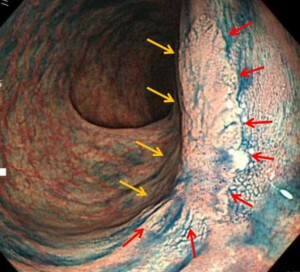

②①のように粘膜内がんという粘膜内にとどまるようながんでも、サイズが大きくなれば入院での内視鏡治療(内視鏡的粘膜下層剥離術)が必要となることが多いです。

③分類では「早期大腸がん」になりますが、粘膜の下の層「粘膜下層」という中の深い層に入り込んでいると大腸の外のリンパ節や肝臓などに転移する可能性がありおなかを切り、大腸の一部とリンパ節を切除する手術が必要となります。内視鏡治療適応外となります。